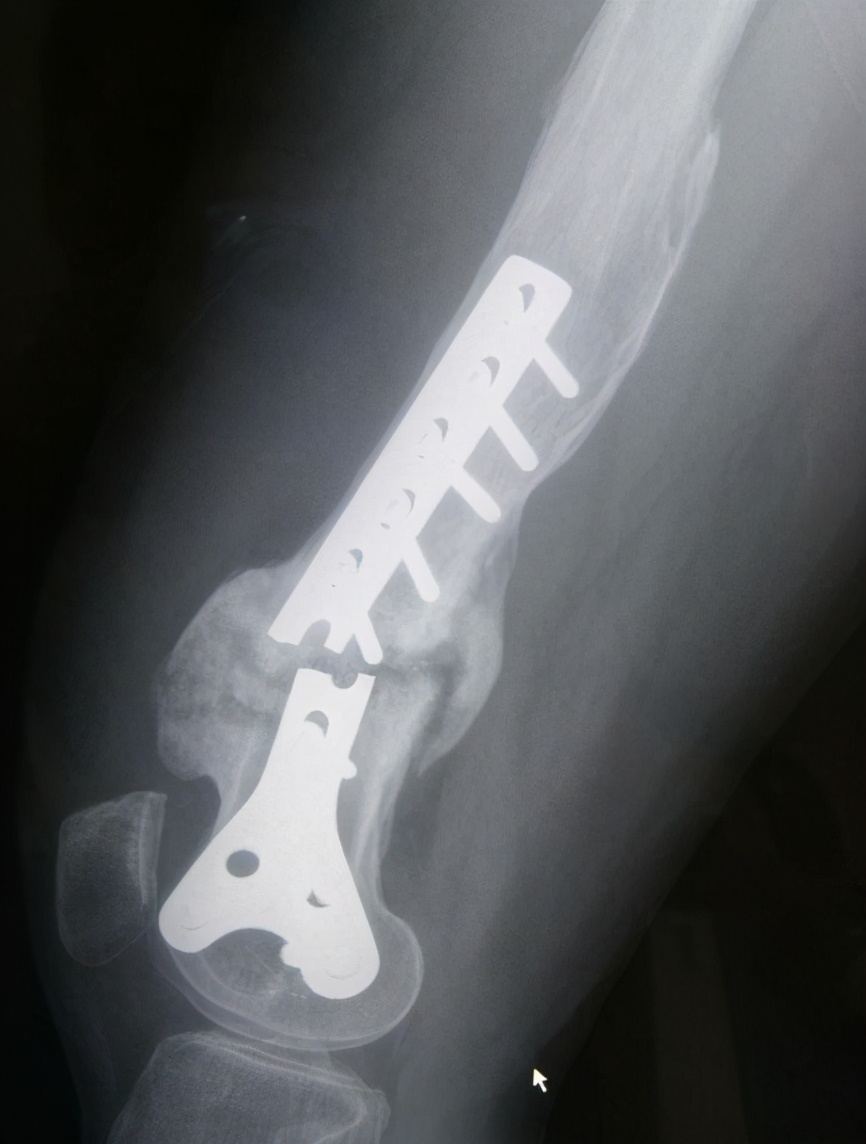

2、特殊部位:踝关节的下胫腓联合螺钉,一般术后6-8周,在下地负重前一定要取掉,否则下地后容易导致螺钉断裂;这是因为什么呢?因为这里的钉子太容易发生断裂了,如果不及时取出的话,一旦断裂,想 在 取出那就难了,事后可能引发关节炎,严重影响生活。

下胫腓联合螺钉